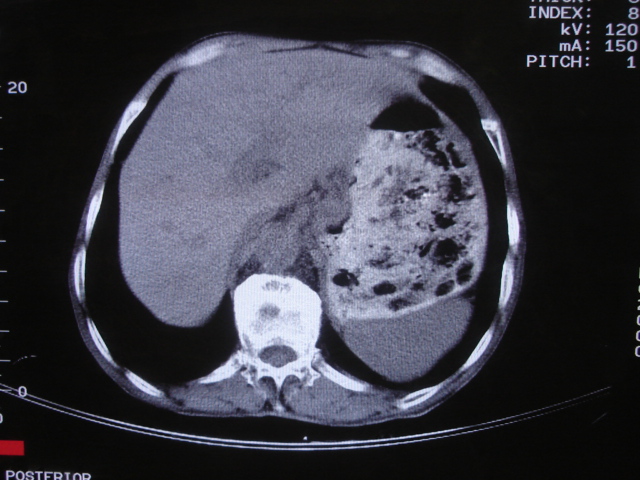

以下是引用深泽交通医院在2008-7-17 12:39:00的发言:[br]胃下垂;胃窦占位